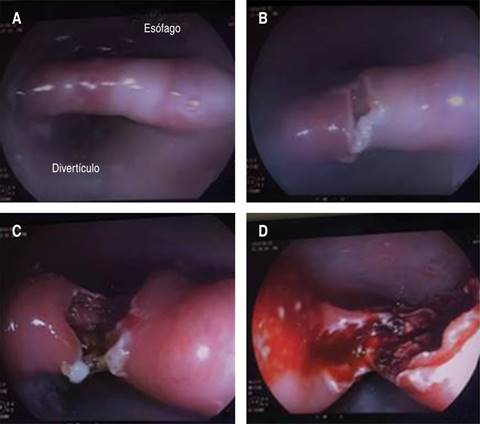

With the established diagnosis of ZD, she underwent an Endoscopic Zenker Diverticulotomy Overtube Assisted procedure utilizing: Fujinon videogastroscope 530ZW; Erbe VIO 200D-electrosurgical unit-endocut mode-effect 2/interval 2/power 40 w; needle knife-Microknife (Boston Scientific); nitinol guidewire (Boston Scientific); resolution clips (Boston Scientific); and soft Zenker Overtube (Cook). The intervention was performed in the Endoscopic Unit, under conscious sedation with midazolam, considered the best option for this frail elderly patient. Illustrative images including the incision of the septum between the diverticulum and esophagus, and myotomy of the septal wall followed by complete myotomy are showed in the Figure 3.

Figure 3: Endoscopic views of the surgical procedure. A) The septum between the diverticulum and esophagus; B) Initial step of the cricopharyngeal myotomy; C) Following phase of the myotomy; and D) Complete myotomy.

The basis of symptomatic ZD management is surgical, and minimally invasive methods as endoscopic myomectomy and diverticulotomy are often utilized.1-6,8-12 The technique used in our patient was endoscopic section of cricopharyngeal muscle and division of the common wall between the diverticulum and esophagus (Figure 3C-D). Advantages of endoscopic option in comparison with the open surgery include shorter duration and lower costs, rapid recovery from anesthesia or sedation, better outcomes, and fewer postoperative complications as fistulas and surgical infections.1,5,6,10-12 However, difficulties related to exposure and the recurrences may enhance failures.8,12